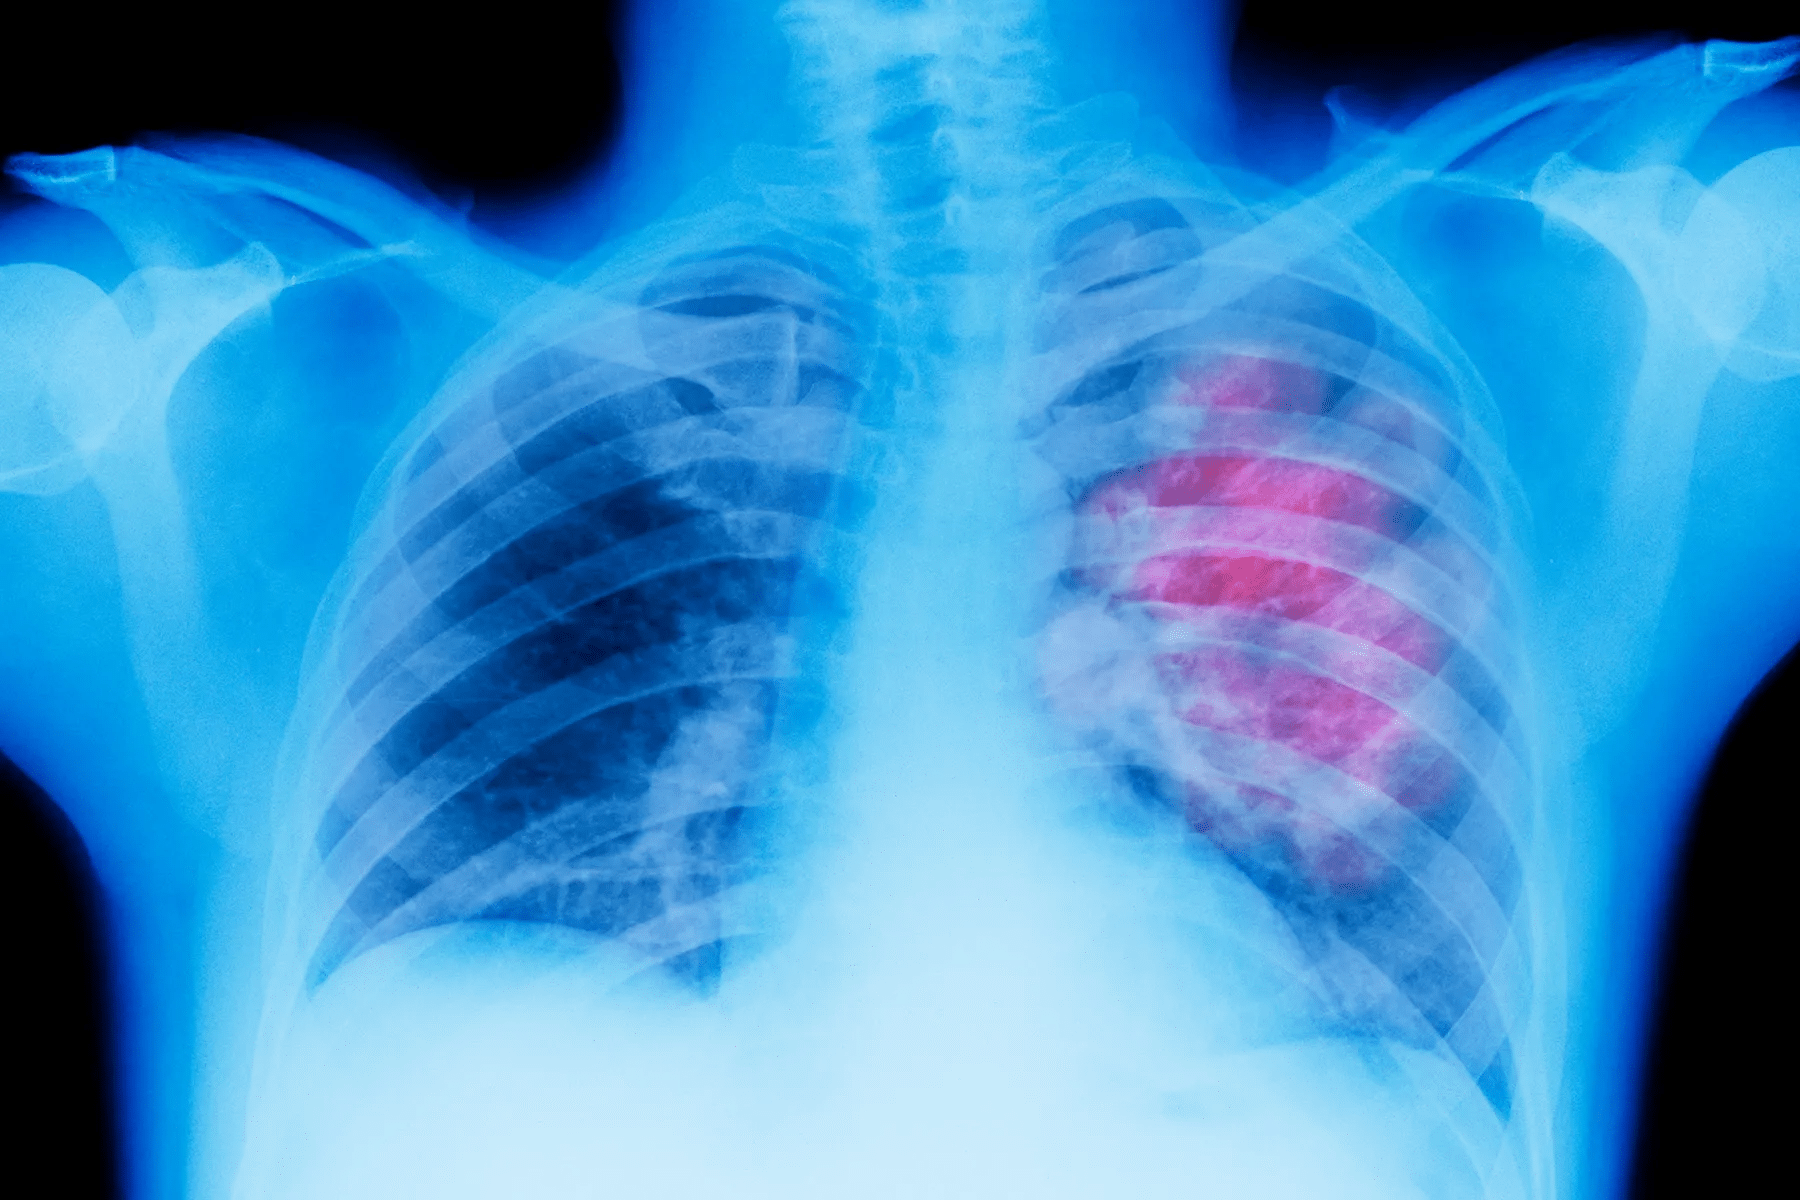

Pneumonia is a serious infection that affects millions. It’s important to understand its stages for better treatment. Pneumonia goes through four stages: congestion, red hepatization, grey hepatization, and resolution.

Understanding Pneumonia: A Brief Overview

Pneumonia is a serious lung infection that affects millions worldwide. It’s important to know what causes it, its types, and how it progresses. This knowledge helps in treating the disease effectively.

Pneumonia goes through stages as the body fights the infection. The four stages – congestion, red hepatization, gray hepatization, and resolution – help doctors understand and treat the disease.

Pneumonia goes through four stages, each with its own symptoms and changes. Knowing these stages helps us understand how the disease grows and how to get better.

Doctors divide pneumonia into four stages based on what they see and what happens in the body. These stages are congestion, red hepatization, grey hepatization, and resolution. Each stage shows a different part of the disease’s life cycle.